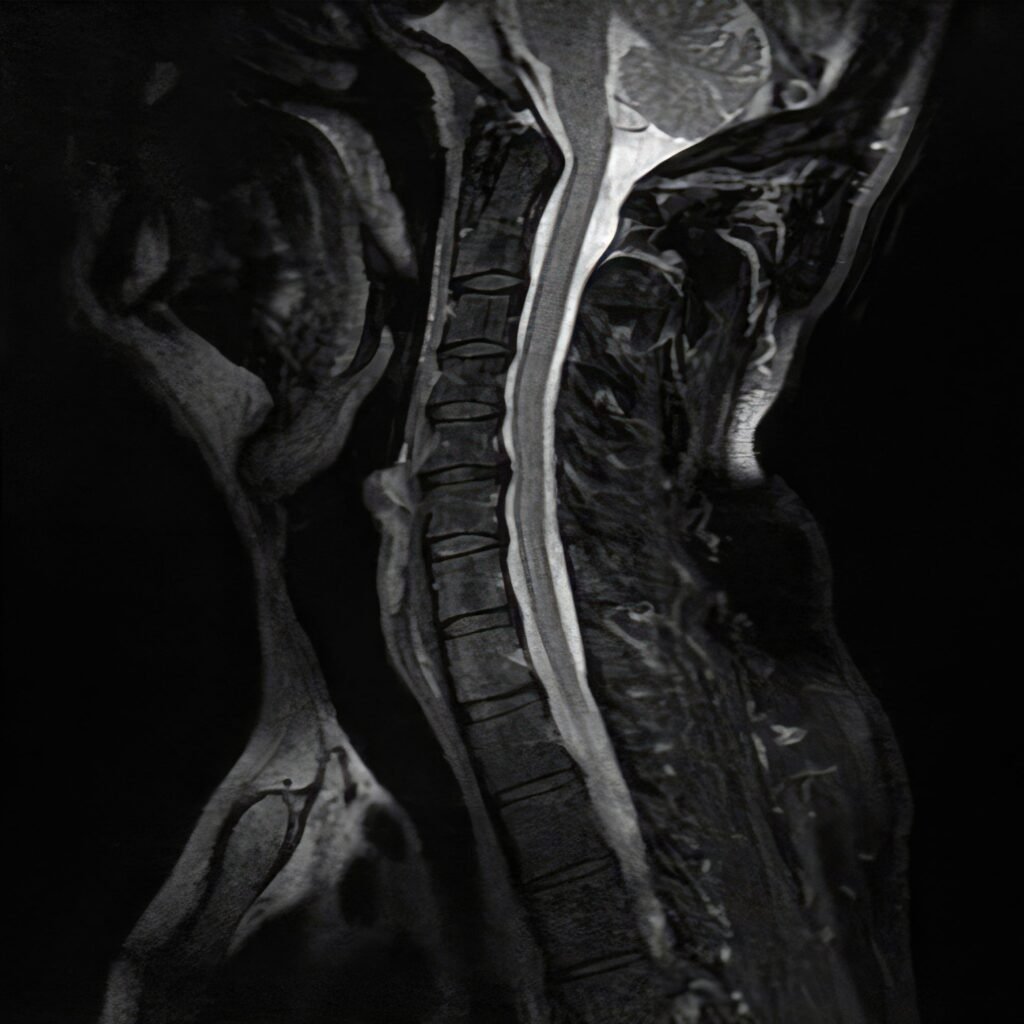

Cervical Spinal Stenosis

Cervical Spinal Stenosis is the narrowing of the spinal canal in the neck, which can compress the spinal cord and nerves. Symptoms may include neck pain, numbness, weakness, or balance difficulties. Treatment ranges from physical therapy and medications to surgical interventions such as decompression or fusion to relieve pressure and preserve function.